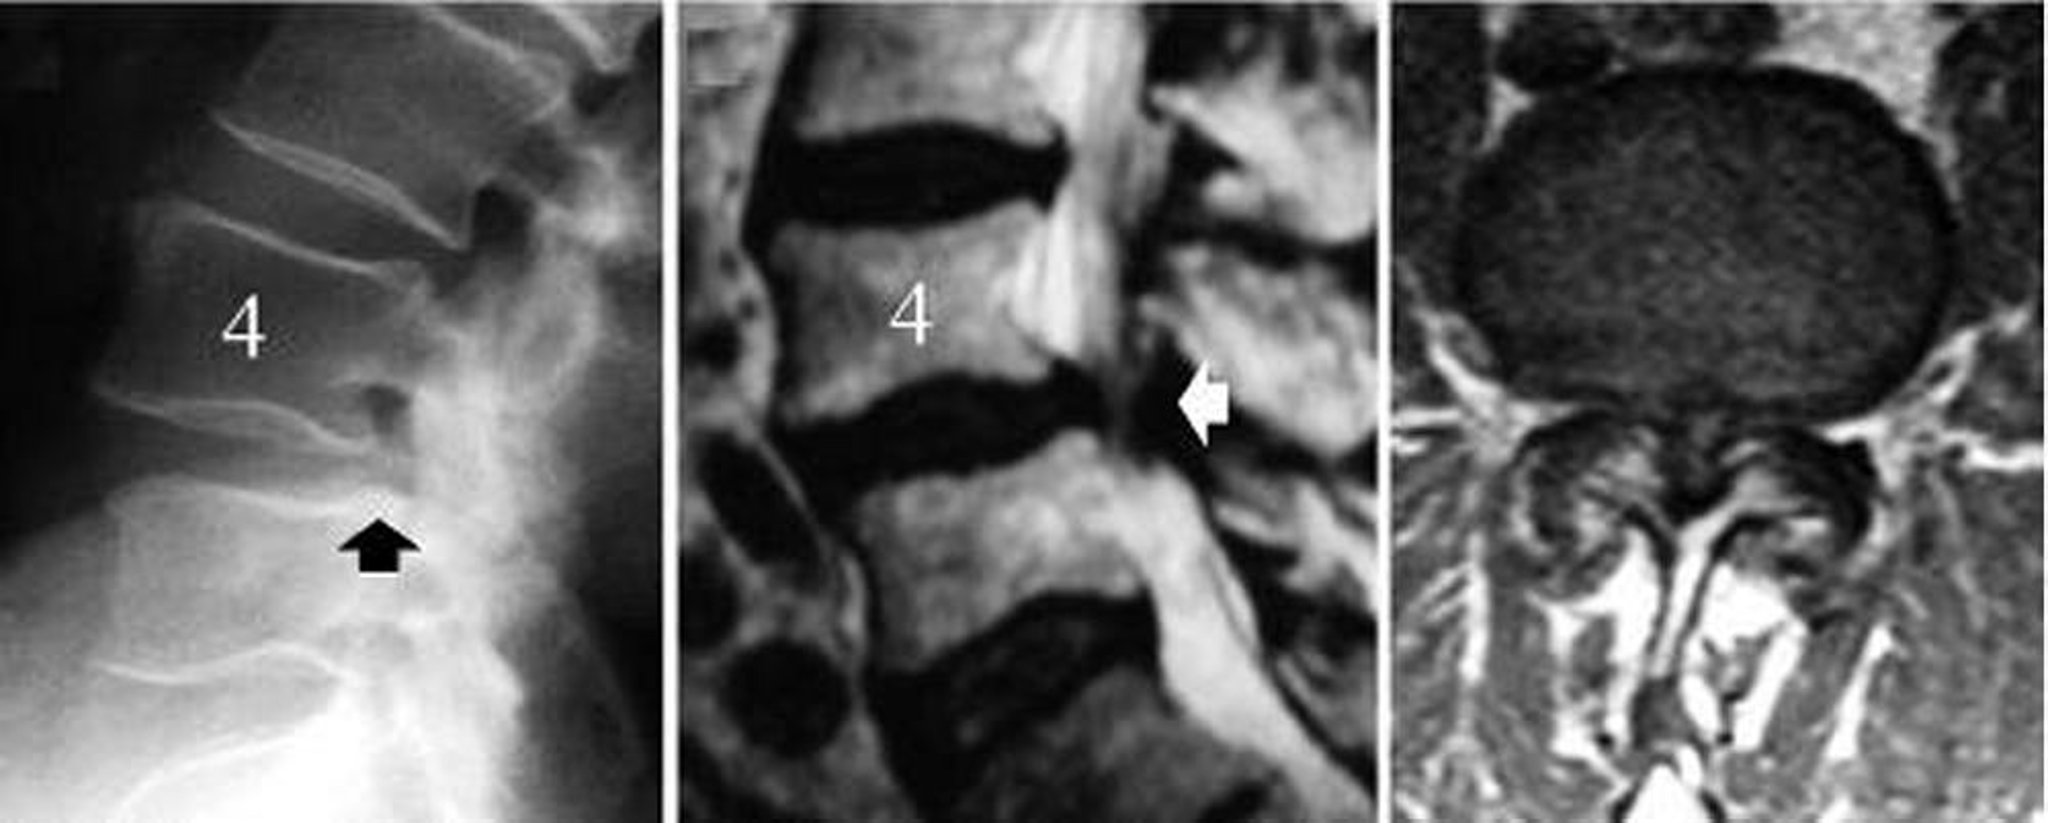

Люмбальный спинальный стеноз, вызванный дегенеративным спондилолистезом позвонка L4-L5

Изображение слева –рентгенограмма в боковой проекции поясничного отдела позвоночника, показывает соскальзывание позвонка L4 (черная стрелка – задняя граница тела позвонка L5 не совпадает с задней границей L4). Изображение в центре является среднесагиттальной МР-томограммой, показывающей компрессию нервных структур (белая стрелка). Изображение справа представляет собой аксиальную МРТ скан, показывающий выраженный стеноз спинномозгового канала на уровне дегенеративного спондилолистеза - L4-5 (белая стрелка).